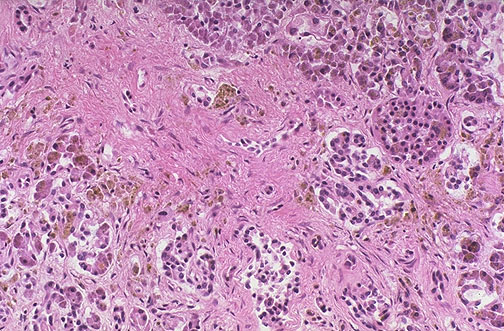

At medium magnification, the pancreas demonstrates interstitial fibrosis, along with extensive iron deposition seen as pale brownish hemosiderin granules.